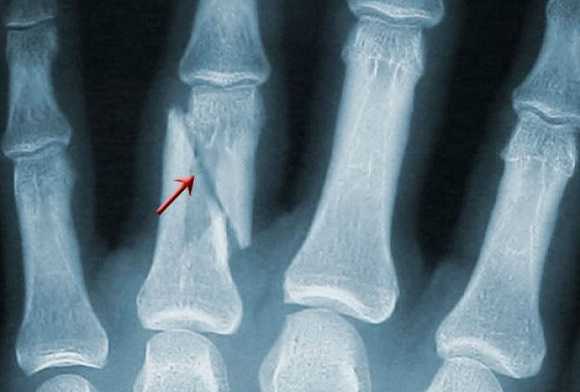

Некоторые костные переломы запястья также трудно увидеть при рентгенографии или даже КТ. Это особенно относится к трабекулярным переломам, типичным для спортивной травмы.

Очень сложны в диагностике переломы ладьевидной кости - они часто пропускаются на рентгенограммах. Осложнением такого перелома может стать асептический ее некроз. На Т2-взвешенных МРТ при переломах виден отек костного мозга, обычно частично охватывающий кость.